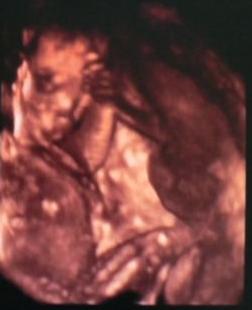

Apa csinált a 4D UH-ról képet. Persze nem a legtökéletesebb a felbontás, de megpróbálom feltenni.

Nagyon jók a képek!!! Kisfiúcskának tűnik nekem! De lehet hogy kislány! :lol: :lol: Láthatóan jól érzi magát bent. Azóta gondolom sokat nézegeted a képeket. Én napokig többször néztem mikor meg lett a fotónk, aztán lemásoltuk és kicsücsültettük a konyhaasztalra hogy sűrűn lássuk. :lol: